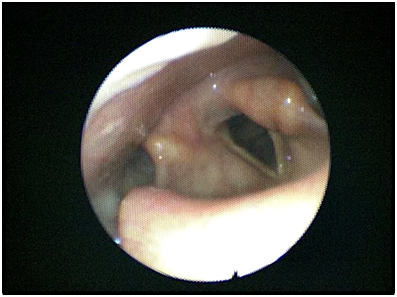

Video laryngoscopy demonstrated left sided vocal cord paresis in a paramedian position without oedema or compression (Figure 2). There appeared to be incomplete compensation of the contralateral cord. The remainder of the endoscopic examination was unremarkable.

Figure 2 Image of flexible nasendoscopy of the larynx performed post-procedure demonstrating complete left sided vocal paralysis.